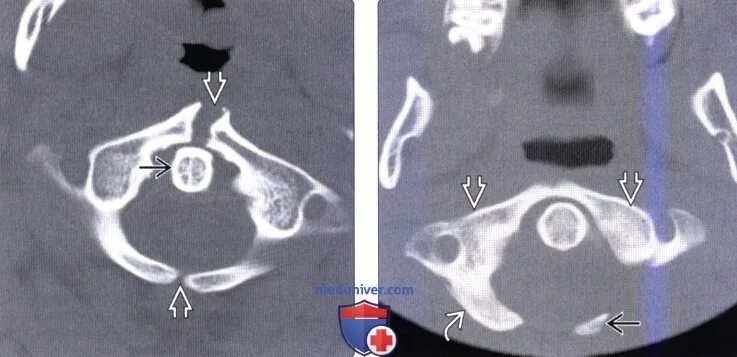

Гипоплазия 12 пары ребер